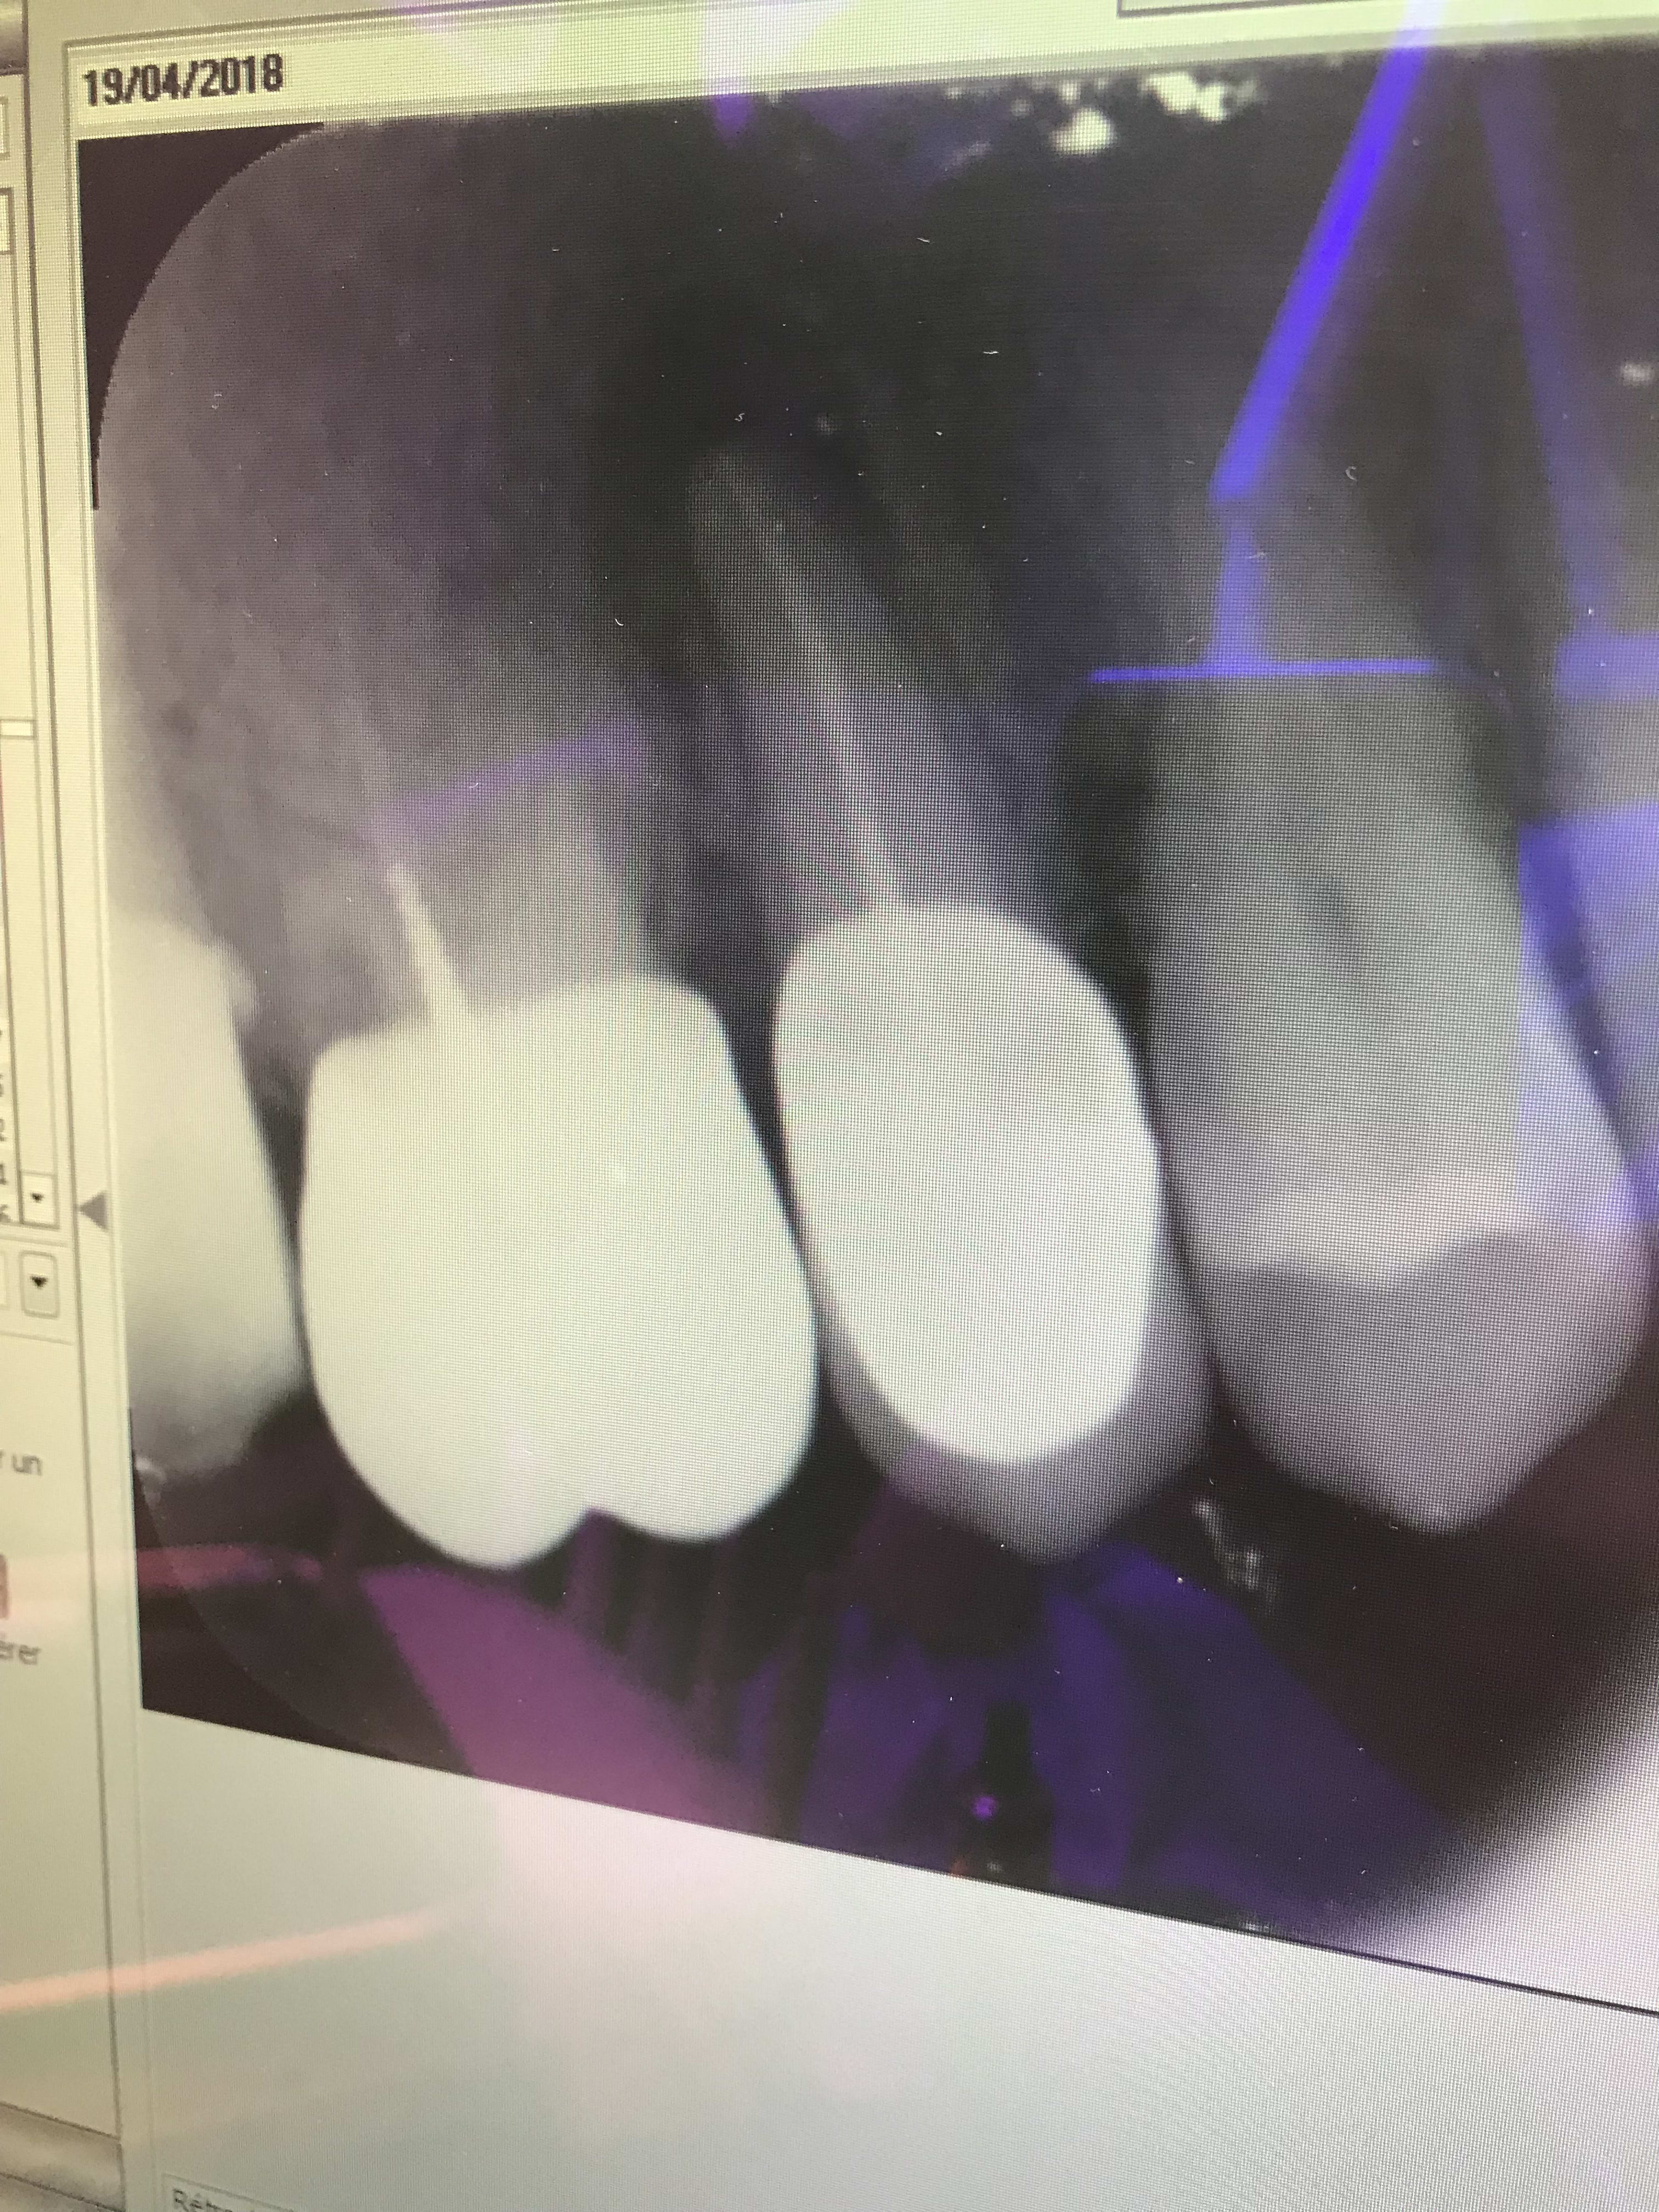

Vu la gueule de la perte tissulaire en distal, elle avait de toute façon un pied dans la poubelle jaune...

Vu la proximité de la branche montante, l'épaisseur de conjonctif dans ce secteur, la lésion infra-osseuse...

L'endo pour quoi faire? Une empreinte dégueulasse et une restauration débordante collée dans la merde?

Ç est vrai qu on dirait 8 mais elle est en position de 7, non ?

La plus a gauche on dirait 1pm